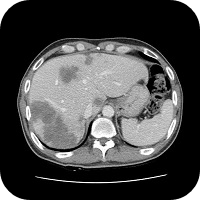

- 전산화단층촬영(CT)

전산화단층촬영(CT, computed tomography)은 대장암 자체의 진단 외에도 종양의 확산을 평가하는데 유용한 방사선 검사법이다. 특히 종양이 장의 벽을 넘어 주변 조직이나 다른 장기를 침범했을 가능성이 있을 때 진단에 큰 도움이 되며, 간이나 폐, 림프절 등으로 전이 여부를 검사할 때 가장 널리 사용되는 검사방법이다.

보통의 전산화단층촬영에서는 전날 특별한 처치를 할 필요가 없으며, 검사 당일에 8시간쯤 금식만 하면 된다.

촬영시 환자아게 정맥주사로 조영제를 주입하는데, 신장(콩팥)의 기능이 떨어져 있는 환자, 당뇨약 중에 메트포민을 복용하고 있는 환자, 이전에 조영제에 대한 알레르기 반응, 즉 심한 구토나 피부나 점막이 빨갛게 부어오른 발적, 두드러기, 가려움증, 목이 붓고 쉬는 듯한 증상을 보인 적이 있는 환자는 사전에 담당의사와 상의해야 한다.

암으로 확진이 된 이후 일반적으로 혈액검사를 통해 암태아성항원(CEA)검사 및 전반적인 환자의 건강상태를 체크하고 CT촬영을 1차적으로 한다.

CT촬영의 목적은 주로 전이여부를 확인하기 위한 것이다. CT소견상 다른 장기에 전이가 확인되면 곧바로 병기가 4기로 진단이 된다. 다만 CT촬영만으로는 그 이외의 정확한 진단하기는 어렵기 때문에 CT촬영 후 2기 및 3기 등의 추정에 불과하다. PET-CT는 CT촬영으로 이상여부가 확인 되었으나, 보다 정확한 진단이 필요할 경우에 촬영을 하게 된다. 이후 수술로 대장암 부위가 절제가 되면 해당 조직에 면밀하게 조직검사를 실시하여 정확한 진단을 하게 된다.